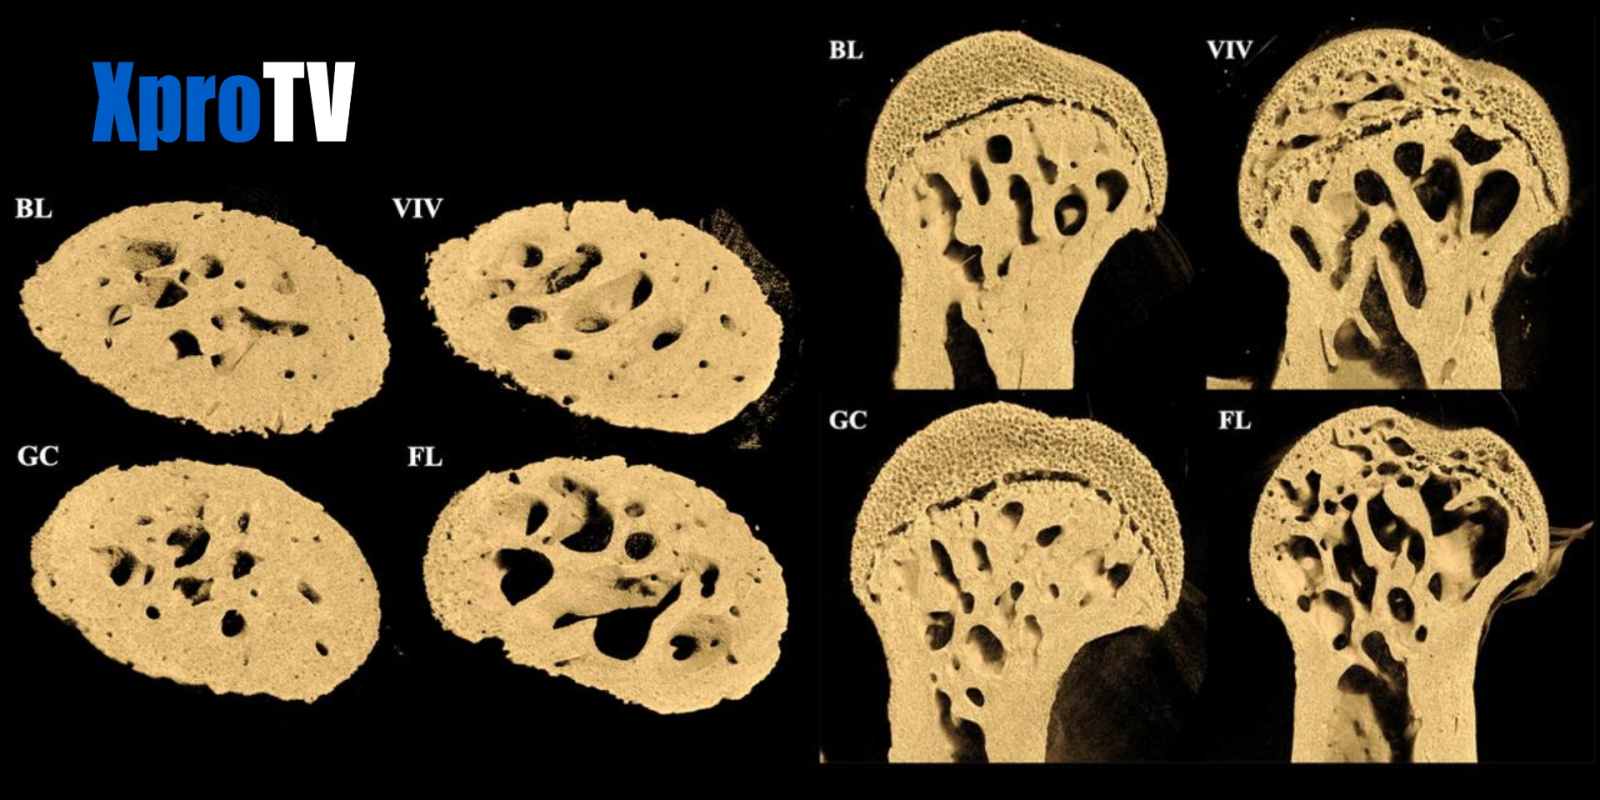

• Los huesos que normalmente soportan peso, como el fémur, sufrieron un grave deterioro.

• Aparecieron grandes agujeros en los extremos del fémur, cerca de las articulaciones de la cadera y rodilla.